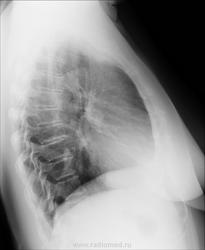

Женщина, 60 лет. Жалобы на общее недомогание, кашель, длительный субфибрилитет. Подскажите, что за округлая тень в правом корне? (Рентгенолога нет, а ответ нужен завтра).

А что с передним нижним углом тела 6 позвонка на боковом снимке?

Эта тень, похоже, и отбражена в проекции правого корня на фасном снимке.Но контуры позвонков склерозированы.опасений.вроде.не вызывает.Сейчас знатоки подойдут и все распишут.

Строение корня такое. Хоть прямой снимок и напрягает, на боковом никакого криминала

Нормальный корень.

Добрый вечер! А пневмонии здесь нет справа?

Вечер добрый.Пневмонии нет.